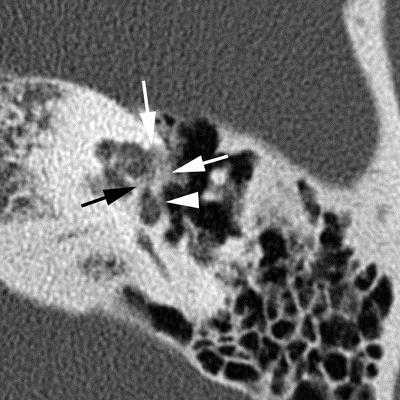

(Слева) При аксиальной КТ правой височной кости у молодого взрослого с прогрессирующей кондуктивной тугоухостью визуализируется типичная отоспонгиозная бляшка (фенестральный отосклероз) спереди от овального окна в области предполагаемой локализации щели перед окном.

2. КТ при отосклерозе:

о Ранние изменения на КТ височных костей:

- Первичные изменения: рентгенонегативный фокус в области переднего края овального окна (ФОто)

- Поражение всех краев овального и круглого окон

- Возможно поражение слуховой капсулы внутреннего уха (КОто)

- Симптом двойного кольца или рентгенонегативное «гало», окружающее улитку, в случае тяжелого КОто

- При прогрессировании болезни возможно поражение любой части костного лабиринта, в том числе латеральной стенки наружного слухового канала

о Поздние, хронические (фаза заживления) изменения на КТ височных костей:

- ФОто: скопления вновь образованной костной ткани вдоль краев овального и круглого окон:

Бляшки могут приводить к окклюзии овального ± круглого окна

- КОто: смешанные рентгенонегативные-плотные очаги в костном лабиринте

(Слева) При аксиальной КТ правой височной кости определяется бляшка смешанной структуры (со склеротическим и «прозрачным» компонентами) спереди от овального окна с вовлечением щели перед окном. Склеротическая часть бляшки при фенестральном отосклерозе обусловлена процессом заживления, рентгенопрозрачная часть - активным процессом.